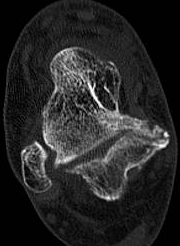

跟骨-足舟骨联合的骨化常常发生在8至12岁,而跟骨-距骨联合的骨化常常发生在12至16岁,开头所说的姚阿姨便是属于跟骨-距骨联合,也就是说姚阿姨可能在青少年的时候就已经出现了跗骨联合。并非所有的跗骨联合都会产生症状,且由于过去经济条件及对此病认识的不足,姚阿姨并没有重视,随着年龄增大,距下关节软骨退变逐渐加重,经过这一次扭伤才意外发现了此病。

箭头所示为跟距联合。